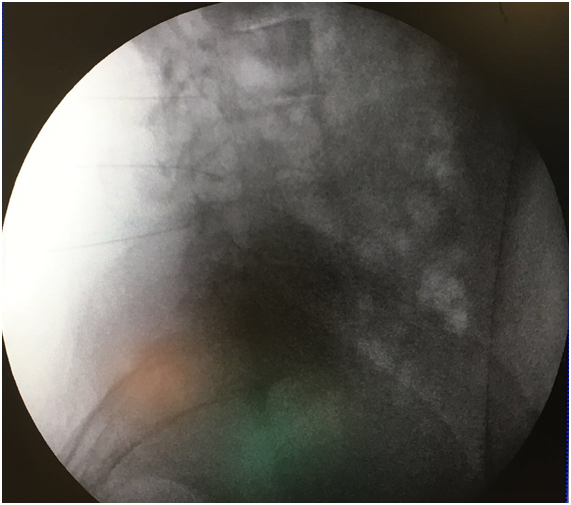

A transforaminal (TF) block was proposed at L2, L3, and L4 on the left side. After explaining the technique and its possible complications, which include the risks of infection, bleeding, and allergic reactions, oral and written consent was obtained, and the nature of the technique was explained to the patient, i.e. to perform a diagnostic block to determine the source of her pain. The technique was performed in the operating room on an outpatient basis, with standard monitoring according to SEDAR [Spanish Society of Anesthesia, Recovery, and Pain Therapy] standards (including EKG, O2 saturation, and non-invasive blood pressure tests) and radiological monitoring. The interventionist located the treatment sites with the patient lying in the prone position, using an abdominal pillow to reduce lumbar lordosis. During the procedure, a Yale 22G spinal needle was used for all treatment sites. The area was cleaned with chlorhexidine solution and misted so that the surgical field was completely sterile, with the area to be treated left exposed. A TF block was performed at the level of L2 without difficulty, although the TF block at the level of L3 was very difficult due to the patient’s anatomy, which presented with a lateral displacement of L3 and abundant osteophytes on the vertebral body, making it very difficult to visualize the entry point through the foramen. For this reason, it was deemed more appropriate to enter through the L3-L4 facet joint. In order to perform the block at this location, the C-arm of the fluoroscope was tilted obliquely until the spinous process was brought to the contralateral pedicle axis, or until the superior articular process could be seen in the middle part of the intervertebral disc, forming the famous “Scottie dog” sign, at an oblique inclination of approximately 20-30º; the double contour of the intervertebral disc was corrected with a craniocaudal inclination of the C-arm. After this maneuver, the X-ray was inclined craniocaudally (20º) to separate the iliac crest and allow entry into the foramen, according to the usual technique.13 Given the impossibility of visualizing the entry point, the C-arm was forced to incline in both directions (obliquely and craniocaudally), without achieving visualization (Figure 1). As seen in Figure 2 the only entry point that allowed access to the desired target was through the zygapophyseal joint. To perform this approach, this joint was centered and the C-arm was rotated until the facet joint could be visualized correctly. The target for this type of approach is the middle part of the joint. The approach was done in “tunnel vision” (the needle was positioned with its axis parallel to the X-rays being emitted), advancing along this direction until it reached the location of the L3 DRG. The depth of the needle was checked using a lateral X-ray view (Figure 3). The needle was pushed slightly deeper through the facet joint until it reached the epidural space and the dorsal root ganglion of L3. Entry into the joint is perceived as a loss of resistance as the needle penetrates the synovial membrane. Once it entered into the joint, the location was verified by injecting 0.1 to 0.3 mL of contrast medium (Figure 4). After verifying that the needle was placed perfectly, local anesthetics and corticosteroids could be injected. In this case, the interventionist used 0.25% bupivacaine and triamcinolone, in an amount not exceeding 1-2 mL.

Figure 3 Lateral view of the transforaminal block. See the entrance through the joint into the L3 space (1).